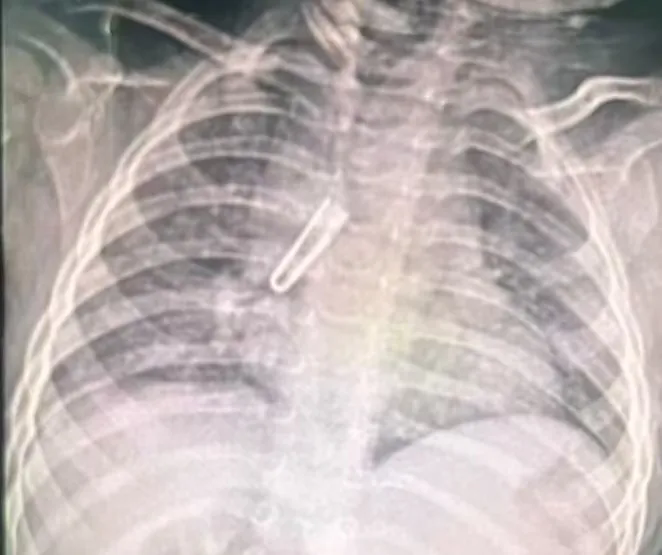

1月6日深夜,一场与时间赛跑的生命救援在焦作市人民医院紧急上演。一名仅11月22天大的女婴不慎误食绳子上的铁皮卡扣,当地医院胸片确诊气管异物后,于当晚11点紧急转诊至焦作市人民医院儿科二区,肺部CT明确显示异物位于右主支气管及中间段支气管腔内,长度达21.1mm,远超婴幼儿气道耐受范围,随时可能引发窒息、气道损伤等致命风险,情况万分危急。

婴儿来院时肺部CT影像

市人民医院迅速启动危重症患儿救治应急预案,儿科二区支气管镜团队与麻醉与手术中心医护团队第一时间集结,在手术室严密监护下开展异物取出术。此次手术难度极大:21.1mm的铁皮卡扣在狭窄的婴幼儿气道内属于“巨型异物”,且呈现“大头朝上”的特殊体位,钳夹后极易因形态不规则卡在声门处,一旦操作不当可能导致异物移位、气道撕裂或窒息等严重后果。